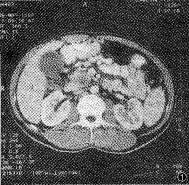

2.1.1 胰腺内异常CT表现:见表1。①病变区胰腺肿大,形成肿块(图1),表现为病变区前后径增大与局限性超出邻近正常胰腺3mm以上的隆起,癌组具有此类表现者49例,癌肿多发生于胰头区(39/49,69.39%)。②病变区密度异常:平扫病变区表现等密度、低密度、低与等混杂密度和更低密度的液化坏死灶。增强扫描绝大多数病灶(49/50,98%)显示为不均匀强化,呈低、等与等混杂和液化坏死的低密度灶(图2)。③胰管扩张:本癌组中胰管扩张率为80%,扩张的胰管均位于肿块的胰尾侧。

图1 胰头癌。平扫示胰头增大,圆隆,其内密度不均,前后径约3.4 cm